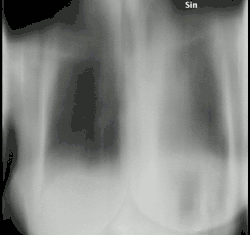

| An example of aspergilloma, one form of chronic pulmonary aspergillosis, following tuberculosis. | |